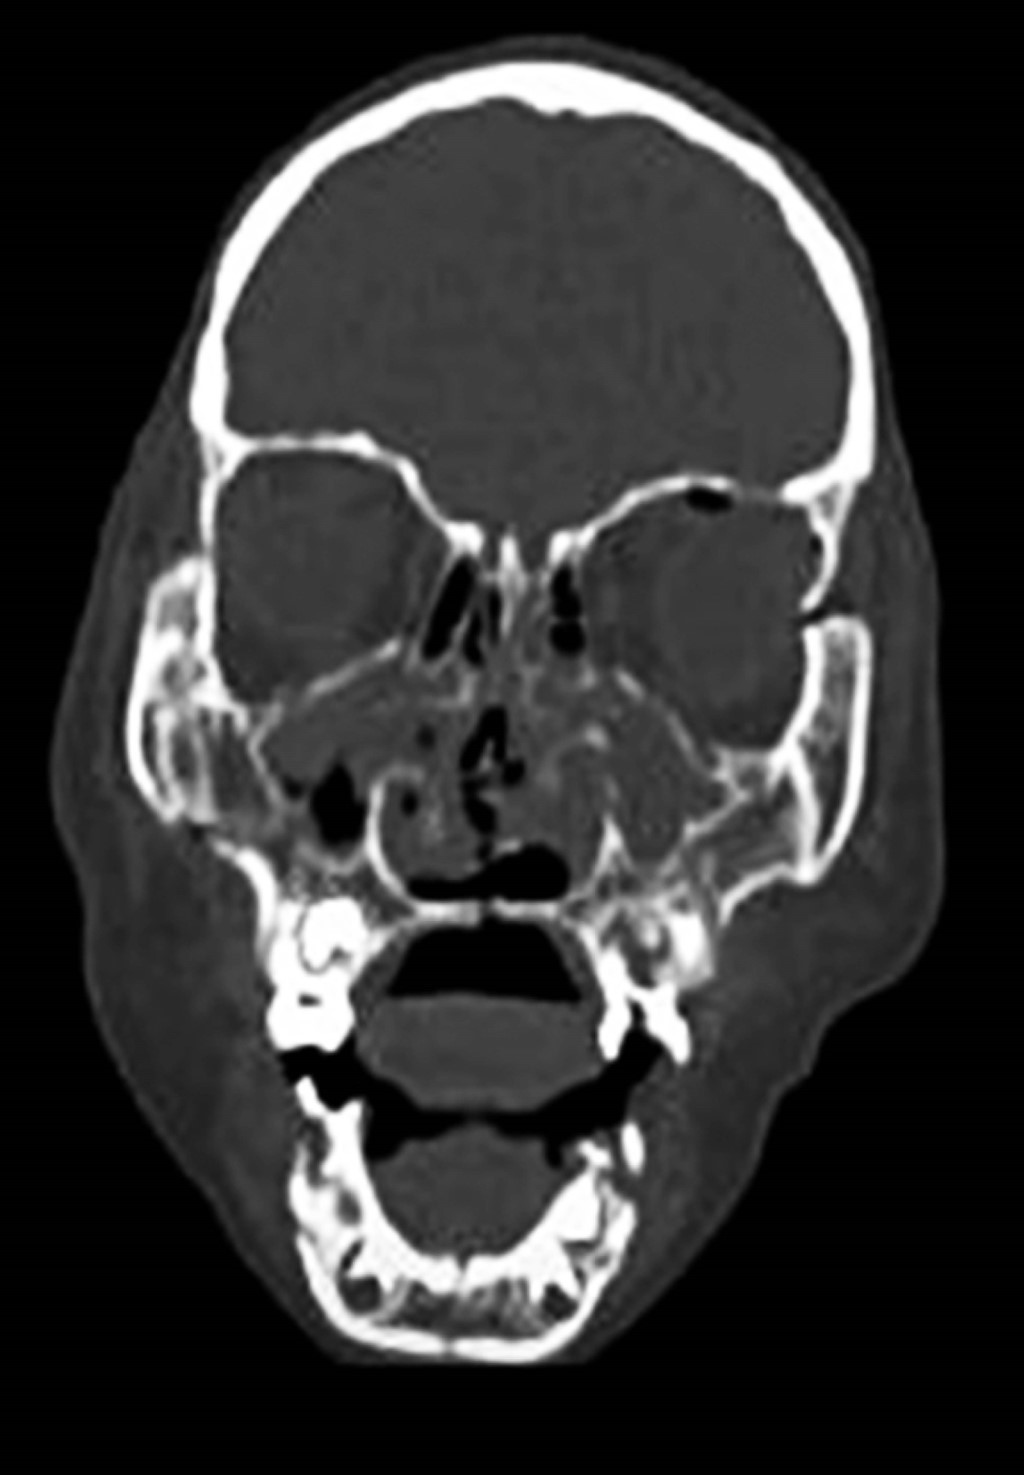

Entre sus antecedentes médicos no se refieren datos de importancia, el paciente inicia su padecimiento aproximadamente a los minutos de impactar con la lavandería sobre la región facial, niega pérdida de conocimiento, vómito o convulsiones. Se descarta compromiso neurológico y se solicita valoración por cirugía maxilofacial. A la exploración física observamos paciente consciente, bien ubicado en sus tres esferas neurológicas de la conciencia, levemente irritado, cráneo sin alteraciones, hundimiento de tercio medio con presencia de equimosis bipalpebral superior, ligera limitación de apertura bucal; a la exploración intrabucal se observa, ausencia de dientes (avulsiones y fracturas de piezas dentarias), paladar con solución de continuidad y mordida abierta (Figura 1). En la tomografía axial computarizada (cortes coronales), con reconstrucción 3D (Figuras 2 y 3), se observan lesiones óseas con solución de continuidad a nivel del tercio medio e inferior y se descarta alguna otra alteración a nivel de tercio superior.

Figura 1

Figura 2

Figura 3